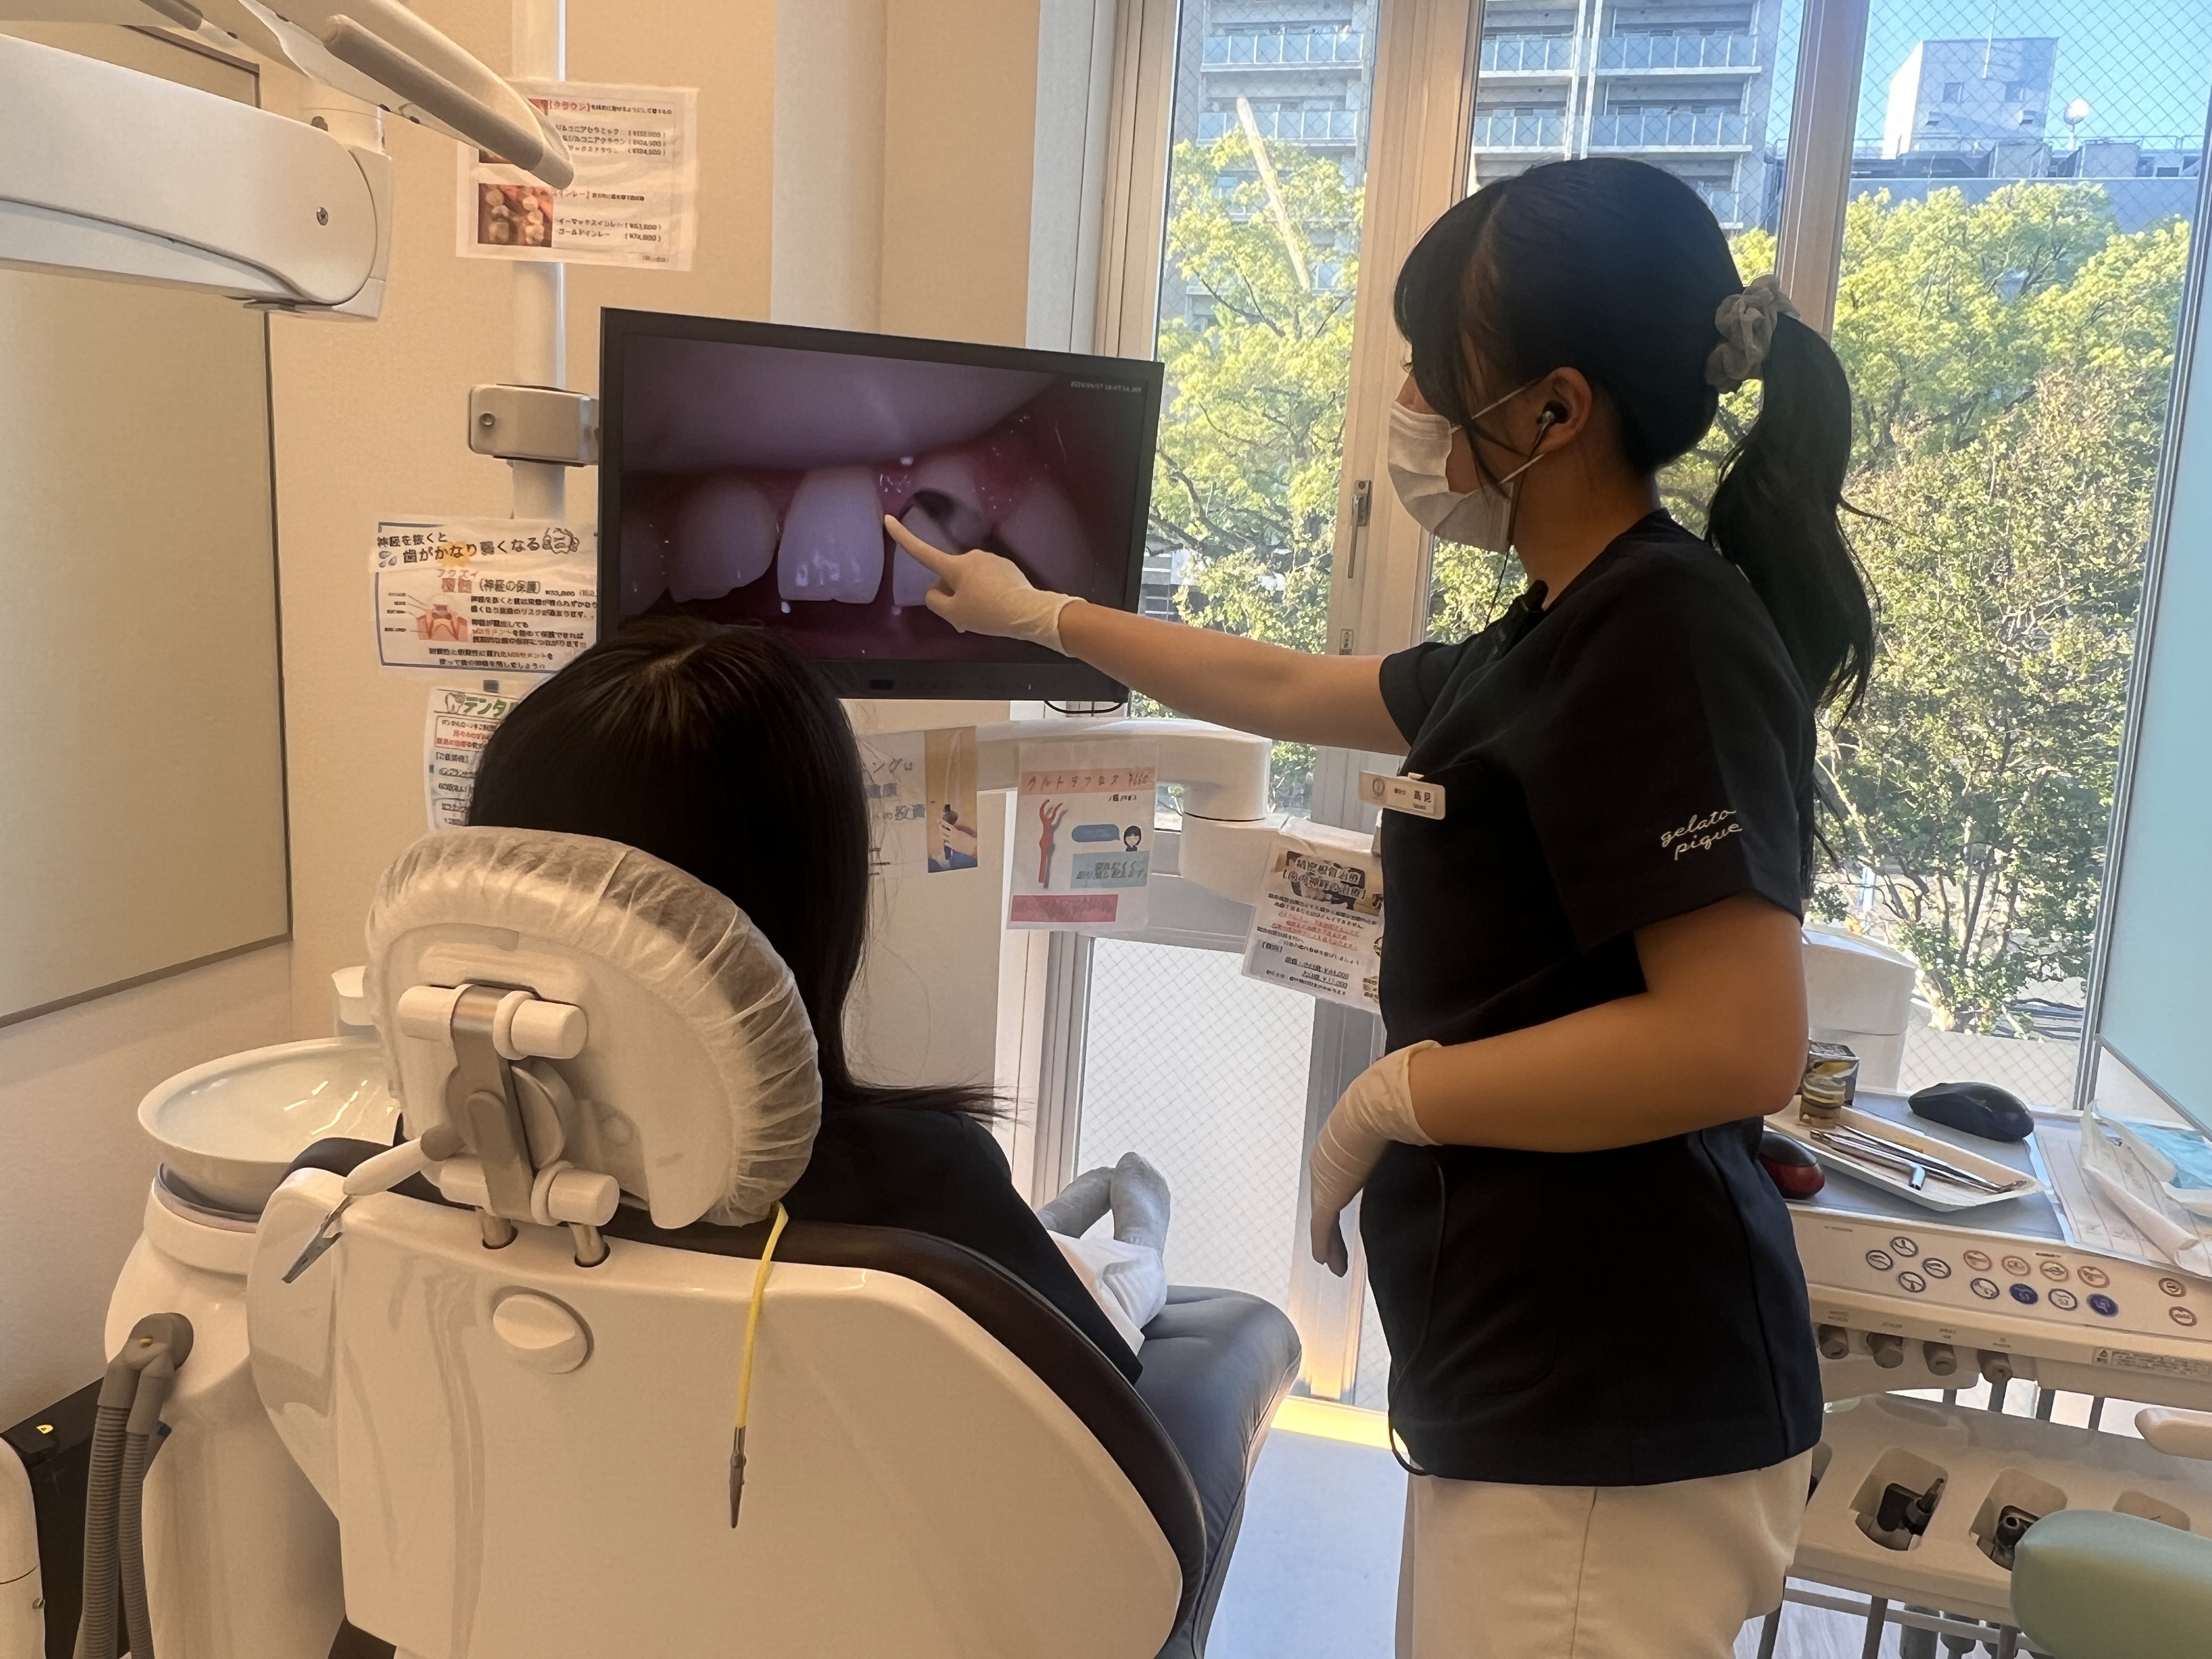

①検査

検診時にマイクロスコープを用いて患者様の口腔内を確認します。

マイクロスコープを用いることによって肉眼では気づけなかった口腔内の変化に気がつくことができます🦷✨

また、マイクロスコープの映像は録画することができるので患者様にも映像を見ていただくことができます🧐

これはプローブという器具を使って歯周ポケットの深さを測定しています。

ポケット検査を行うことによって歯周病かどうかを判断します。